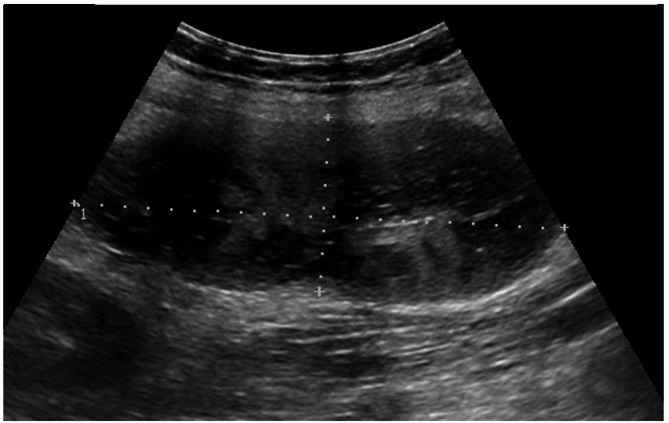

Case presentation: We report on a 14-year-old girl who presented with a 3-day history of left lower abdominal pain and vomiting, with a known history of congenital heart disease associated with Situs Viscerum Inversus and polysplenia. She was found to have normal vital signs but elevated C-reactive protein, and leukocytosis with neutrophilia. In light of the clinical and laboratory data, in addition to the suggestive imaging findings revealed on US and contrast-enhanced abdominal CT, a splenic torsion was suspected. The patient underwent a laparotomy, which confirmed a pedunculated mass in the left flank and iliac fossa, consistent with torsion of one of the spleens, and allowing complete resection of the lesion. The postoperative course was uneventful, and she was discharged after 10 days.